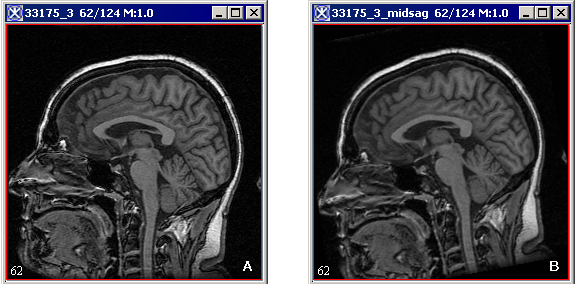

Figure 2. The original image (A) and the image after applying the midsagittal line alignment algorithm (B).

The algorithm begins to run and several windows appear with the status as shown in Figure 3. When the algorithm finishes running, the aligned image appears in a new image frame as shown in Figure 2-B.